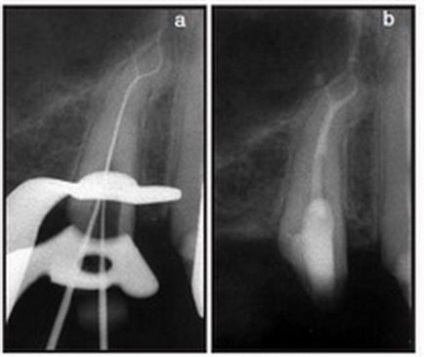

Klinikai eset №7.

a) A harmadik mandibuláris moláris jeleivel akut apikális periodontitis.

b) kitöltése a gyökércsatorna rendszer feldolgozása után a hibrid technikával acél Mtwo rendszerfájlok és eszközöket. Apikális méret # 25 alkalmazásával értük acél fájlt.

c, d) Amennyiben ismételt vizsgálat után 6 hónap (balra) és 1 év (jobbra) ünnepelte a gyógyulás a kóros hangsúly.